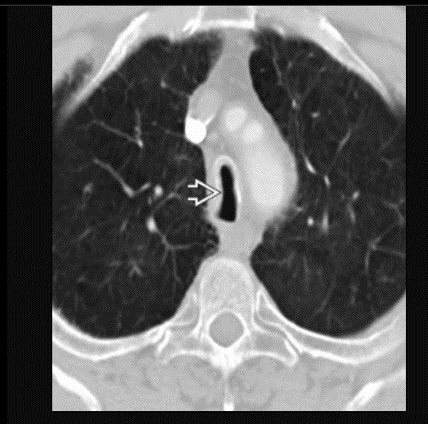

Saber sheath trachea, pathognomonic for COPD

Best diagnostic clue: Side-to-side narrowing of intrathoracic trachea

In this case you can see subtle apical centrilobuar emphysema